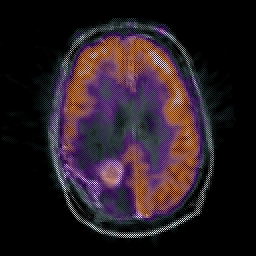

Glioma Overlay -- Slice #14

[Home][Help][Clinical] Slice 14